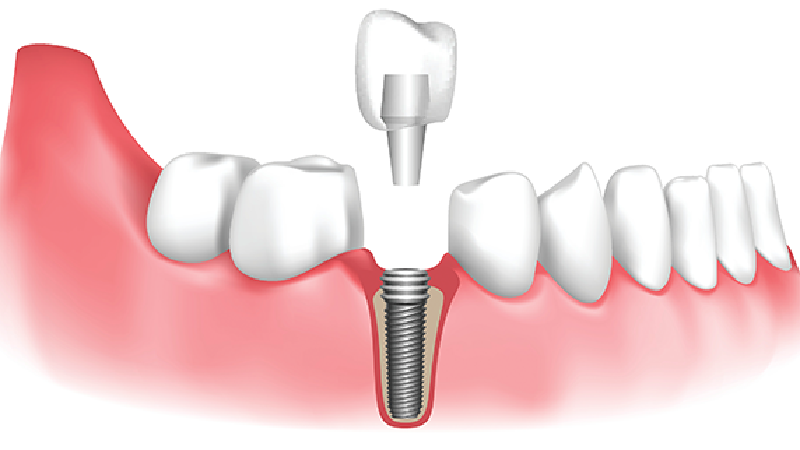

جای گذاری اصولی پایه ایمپلنت درون فک

جایگذاری فیکسچر ایمپلنت دندان درون استخوان فک: ۱۵ تا ۲۰ دقیقه

قرار دادن اباتمنت روی ایمپلنت: ۳۰ تا ۶۰ دقیقه

انجام ایمپلنت فوری دندان از پرطرفدارترین انواع روش ایمپلنت بوده که در فرآیند کاشت آن پس از درآوردن ریشه، بین ۴ تا ۷ ماه زمان برای ترمیم شدن استخوان فک نیاز است. هنگامی که ریشه دندان را از استخوان فک و لثه خارج میکنند، بلافاصله جای خالی آن حفره، با فیکسچر پر میشود و ایمپلنت به بافت های اطراف پیوند خواهد شد.

قرار دادن پایه ایمپلنت درون لثه بلافاصله پس از کشیدن دندان: ۱۰ تا ۲۰ دقیقه